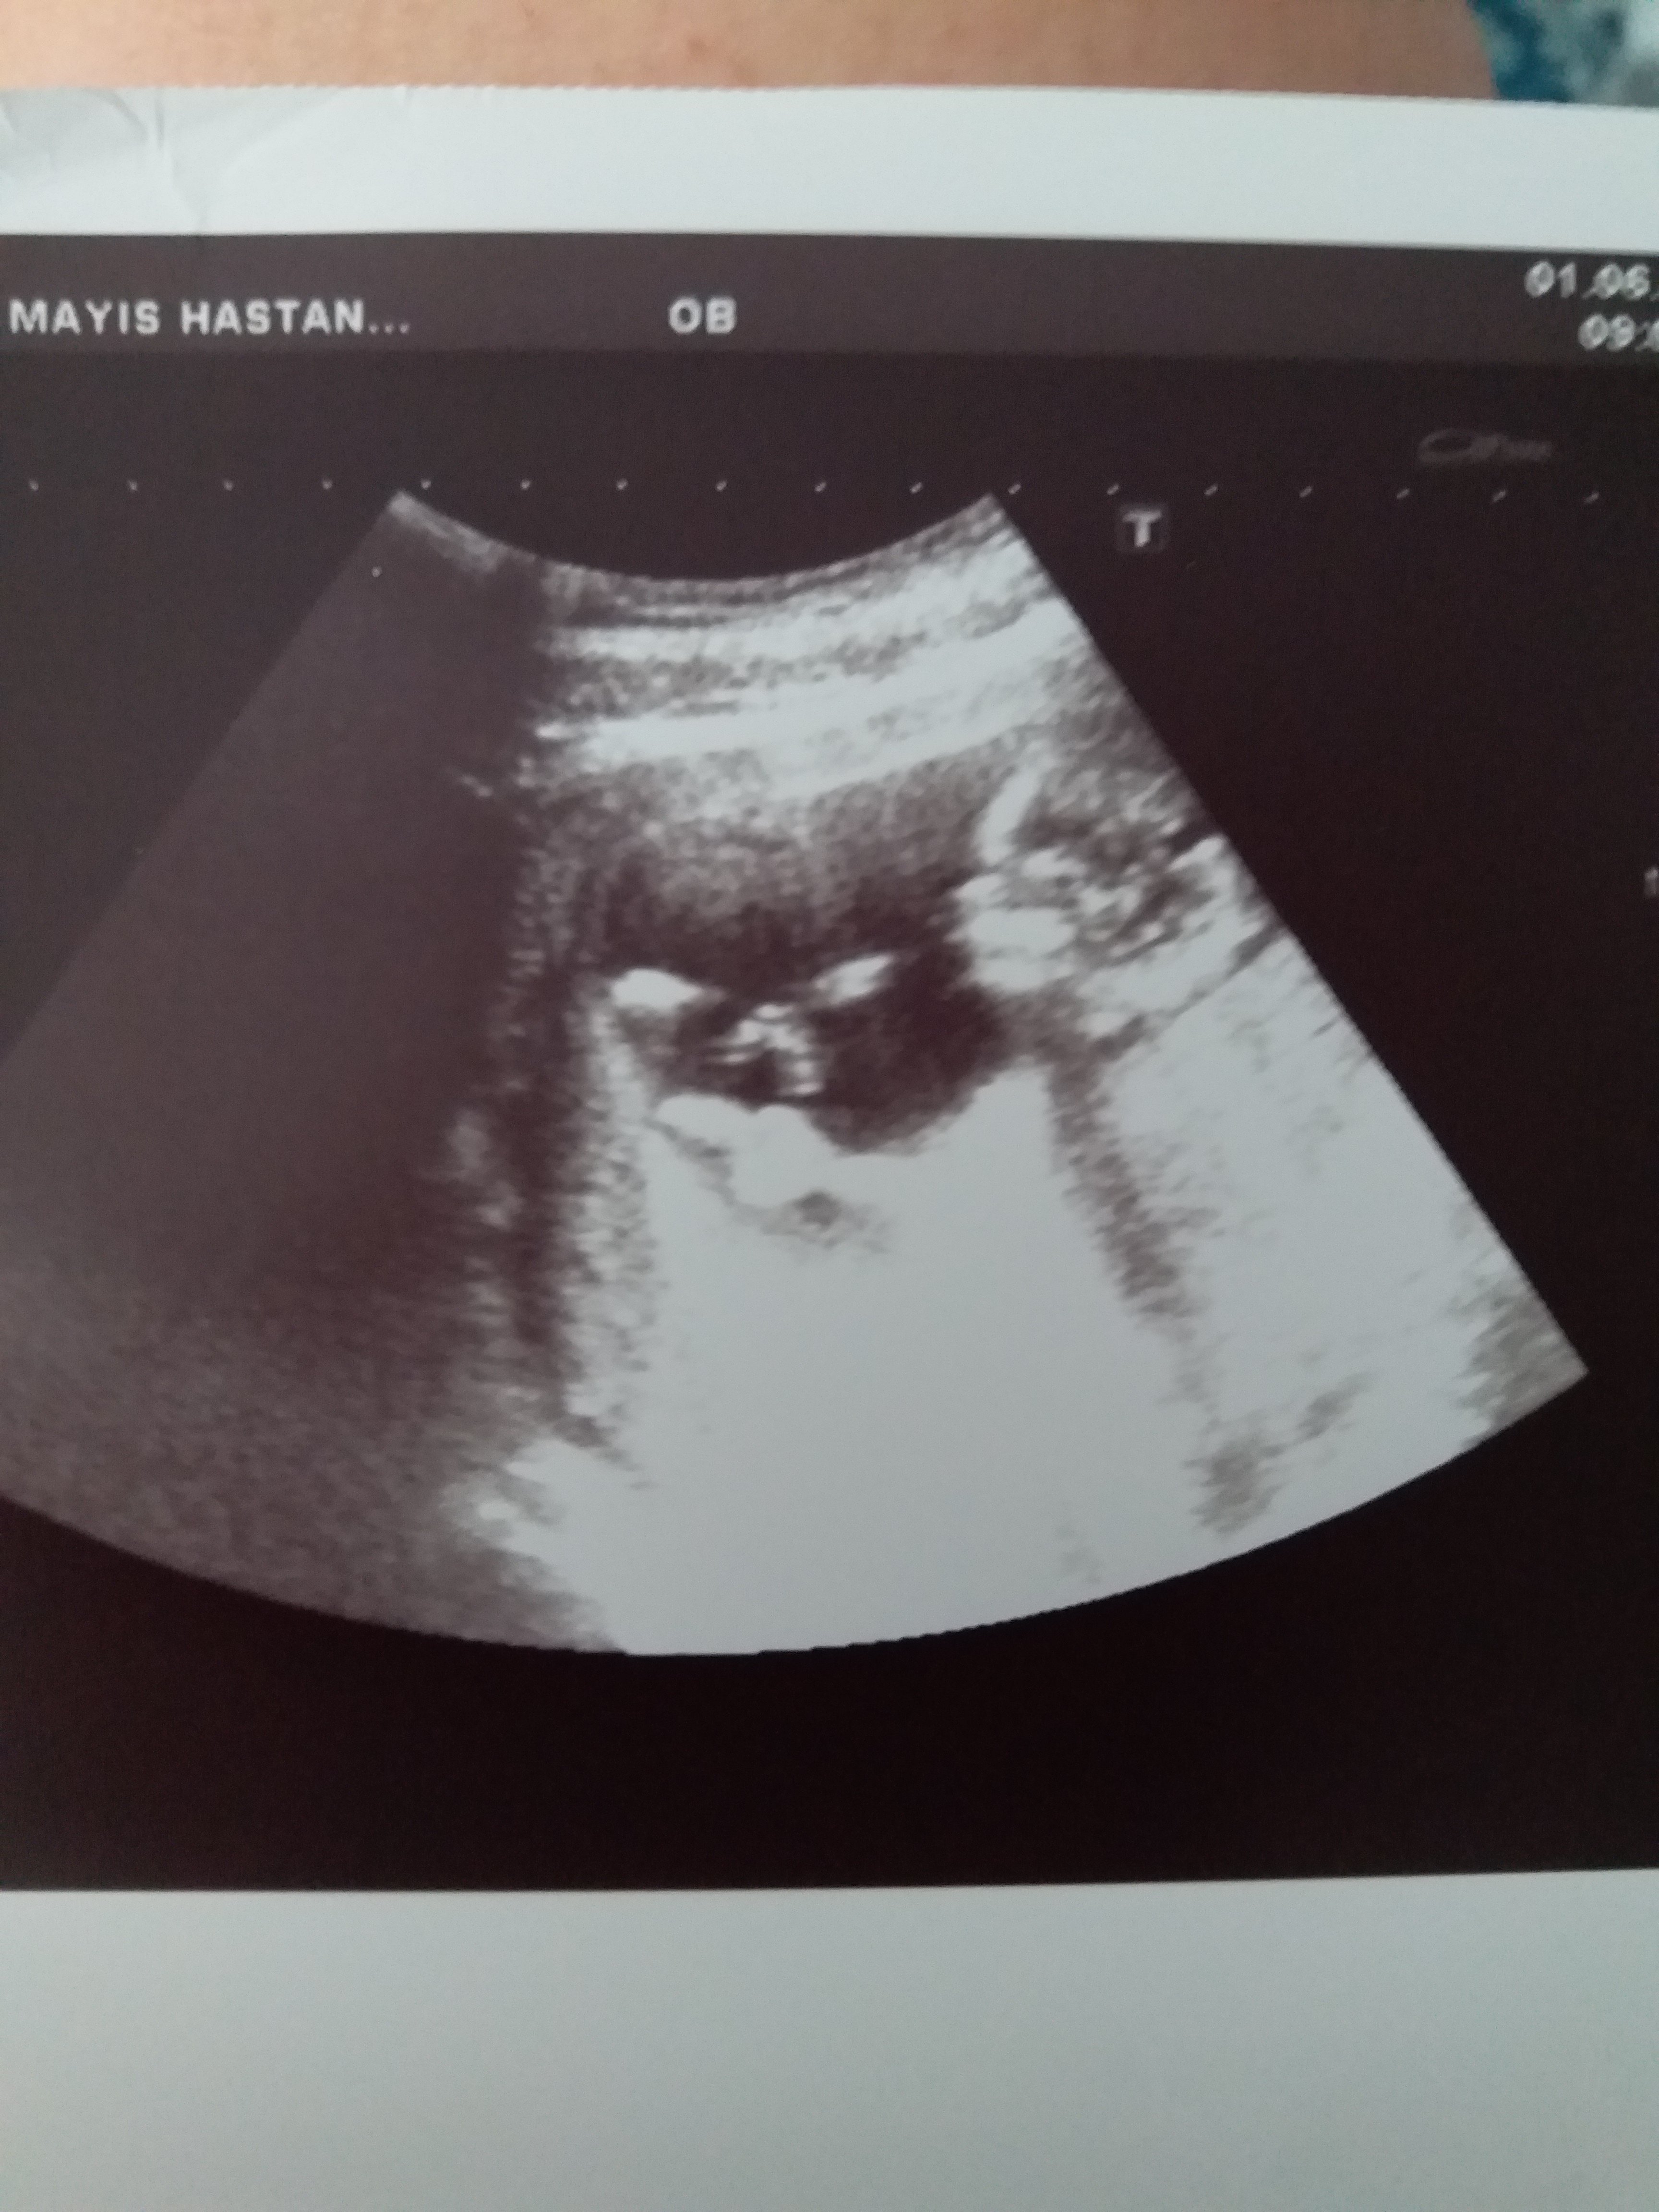

Nub cinsiyet tahmini tutanlar beni de değerlendirir misiniz lütfen ?

Sizce cinsiyet nedir ya bu hafta tekrar gittim doktora net konuşmadı 12 haftadayız lütfen bilen Allah rızası için yardımcı olsun